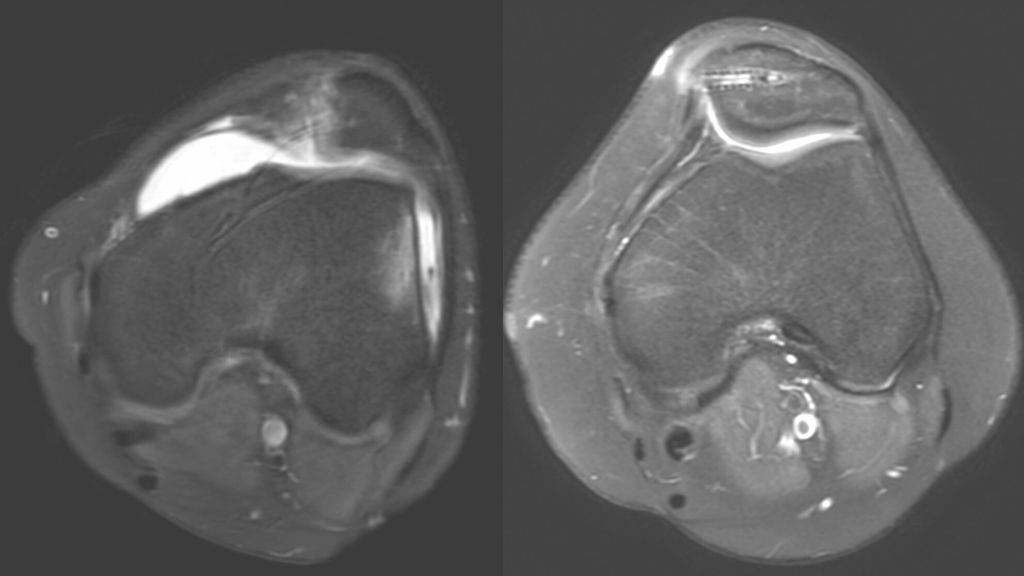

Eine Instabilität bis circa 30° ohne weitere Auffälligkeiten in der radiologischen Untersuchung wird mittels alleiniger MPFL-Rekonstruktion stabil. Ab circa 0–60° Instabilität gibt es zumeist Probleme mit der knöchernen Führung. Dies kann aufgrund eines zu späten Eingleitens der Patella – einer Patella alta – und/oder des Fehlens einer knöchernen Führung (Trochleadysplasie) auftreten. Unserer Meinung nach bedarf es einer Korrektur der Patella alta ab einem Caton-Deschamp-Index >1,2 (Abb.1) und/oder einer LTI (laterale Trochleainklination) von <17° (Abb. 2). Ab 60° ist zusätzlich ein Problem im Bereich des Alignments wahrscheinlich. Bei einer vermehrten Innenrotation des Femurs und der Tibia bei ca. 35° und/oder valgischer Beinachse ab ca. 5° wird eine Korrektur in Erwägung gezogen (Abb.3). Prinzipiell sind wir bei einer Alignmentkorrektur eher zurückhaltend (von manchen Autoren wird bereits eine Korrektur ab 20° Innenrotation empfohlen).5 Ein vermehrter TTPCL-Abstand (lateraler Kraftvektor der Patella) ab circa 24mm kann die Luxation ebenfalls begünstigen und bei einer Patella alta mitkorrigiert werden. Sollte eine knöcherne Stabilisierung notwendig sein, ist bei der Trochleaplastik eine arthroskopische oder offene Technik möglich.

Ablauf der arthroskopischen Trochleaplastik

Der Patient befindet sich in Rückenlage. Begonnen wird die Operation ohne Blutsperre. Wichtig ist ein gutes Zusammenspiel mit der Anästhesie. Der Blutdruck sollte nicht über 90mmHg systolisch steigen (junge Patienten ohne wesentliche Vorerkrankungen tolerieren diesen Blutdruck meist ohne Probleme). Zusätzlich zu den Standardportalen benötigt man ein proximal-laterales Arbeitsportal und ein proximal-mediales Portal für das Arthroskop. Mittels HF-Instrument wird das Fettgewebe gelöst (Abb. 4) und der subchondrale Knochen mit einer 4-mm-Fräse entfernt (Abb. 5). Um das Knorpelknochenschild biegbar zu machen, wird der Knochen noch mit einem „PowerRasp“ ausgedünnt. Die Knochenbrücken am lateralen und medialen Rand müssen noch mit dem Meißel gelöst werden. Über das anteromediale oder anterolaterale Portal bringt man den Push-Lock-Anker mit einem Vicryl-Tape und einem Vicryl-Sicherungsfaden (Abb. 6) ein, dieses wird nach proximal und lateral mit zumindest zwei weiteren Push-Lock-Ankern aufgespannt (Abb. 7). Nach jeder Trochleaplastik wird eine MPFL-Plastik durchgeführt. Eine Distalisierung der Patella kann auch ohne Probleme nach einer arthroskopischen Trochleaplastik durchgeführt werden. Lediglich Derotationen oder Achskorrekturen profitieren unserer Meinung nach derzeit nicht von einem arthroskopischen Vorgehen. Von 2014 bis 2020 wurden 82 Trochleaplastiken an unserer Abteilung durchgeführt, ungefähr die Hälfte davon arthroskopisch. Unsere Nachuntersuchungen konnten keinen wesentlichen Unterschied zwischen den radiologischen und klinischen Ergebnissen zeigen (Abb. 8). Jedoch geht klar hervor, dass die Patienten schneller mobilisiert und aus dem Krankenhaus entlassen werden konnten. Auch die geringere Narbenbildung darf besonders bei einer jungen Patientenklientel nicht außer Acht gelassen werden. Nach einer etwas längeren Lernkurve nähert sich die Operationszeit der offenen Technik an. Kontraindikationen für eine Trochleaplastik sind Arthrosegrade ab Grad III und fehlende Bereitschaft für die doch teils langwierige Nachbehandlung. Bei jüngeren Patienten wurde auch bei Knorpeldefekten die Operation zur Stabilisierung als „salvage procedure“ mit Knorpeltransplantationsangeboten durchgeführt. Es konnten zwar kurzfristig die Schmerzen reduziert werden, auf längere Sicht zeigte sich jedoch – bis auf die Stabilisierung der Patella – keine wesentliche Verbesserung. Besonders bei jungen Patienten sollte die Trochleaplastik in Erwägung gezogen werden, um eine Versorgung mittels Teilendoprothese im jungen Alter zu vermeiden.